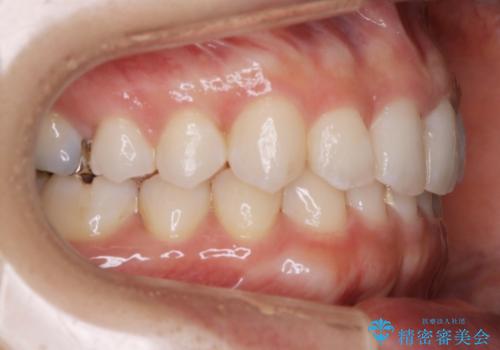

【非抜歯】下の前歯が1本少ない場合の矯正治療

- 前歯のガタつきを主訴に来院されました。

生まれつき下の前歯が1本少なく、その分のスペースを上の前歯がガタつくことで埋めているという状況でした。

上下それぞれのガタつきをとっていく過程で、歯1本分のスペースの差を、上顎の前歯のIPRで調整して並べる方法をご提案させていただきました。